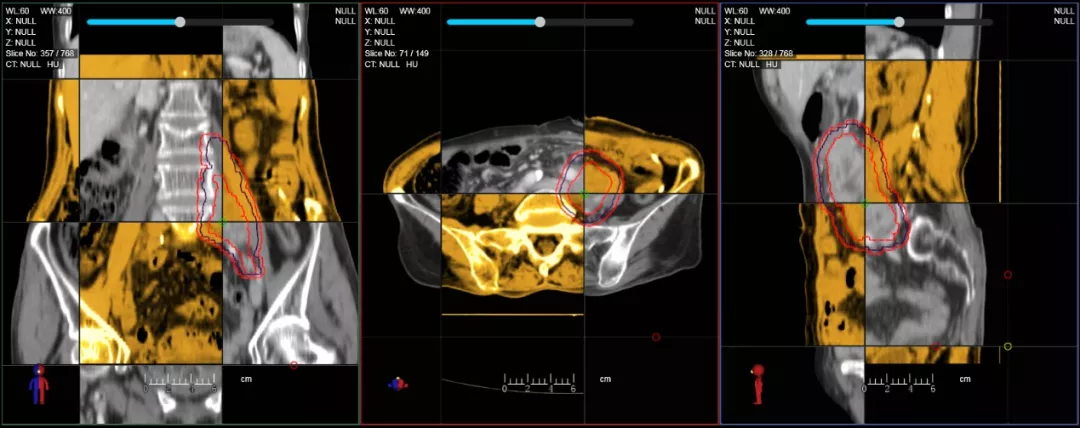

CT-IGRT配準(zhǔn),除骨性標(biāo)記外,還能以器官、軟組織等作為參考,真正找到配準(zhǔn)目標(biāo)

在線自適應(yīng)放療流程示意圖